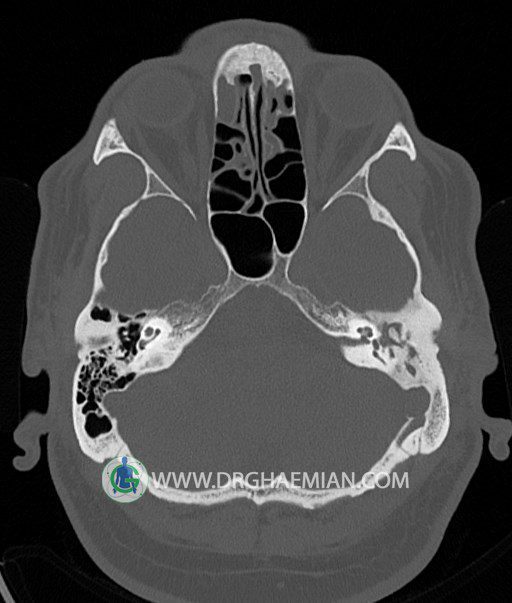

سی تی اسکن گوش داخلی به رادیولوژیست اجازه می دهد تا سطوح مختلف، یا اسلایس هایی از استخوان های که از جمجه به گوش می روند را از طریق امواج ایکس چرخشی مشاهده کند. در این کیس اودیت مدیا، ماستوئیدیت مزمن، اوتیت خارجی، انحراف سپتوم بینی، کونکا بولوزا و افزایش ضخامت سینوس ها مشاهده می شود.

در HRCT از استخوان تمپورال با مقاطع آگزيال ، ساژيتال و کرونال ظريف ( 0.6 mm ) :

– اپاسيتي گوش مياني چپ ناشي از وجود دانسيته نسج نرمي دراطراف استخوانچه ها همراه با اروژن اسکوتوم و

استخوانچه ها بدون جابجايي در رديف استخوانچه ها مشهود است که مطرح کننده اوتيت مديا همراه با نشانه

هاي مشکوک به کولستئاتوم مي باشد .

– اپاسيتي و اسکلروزيس ماستوئيد چپ نشانه ماستوئيديت مزمن

– اپاسيتي کانال گوش خارجي ناشي از دانسيتي نسج نرمي مطرح کننده external otitis